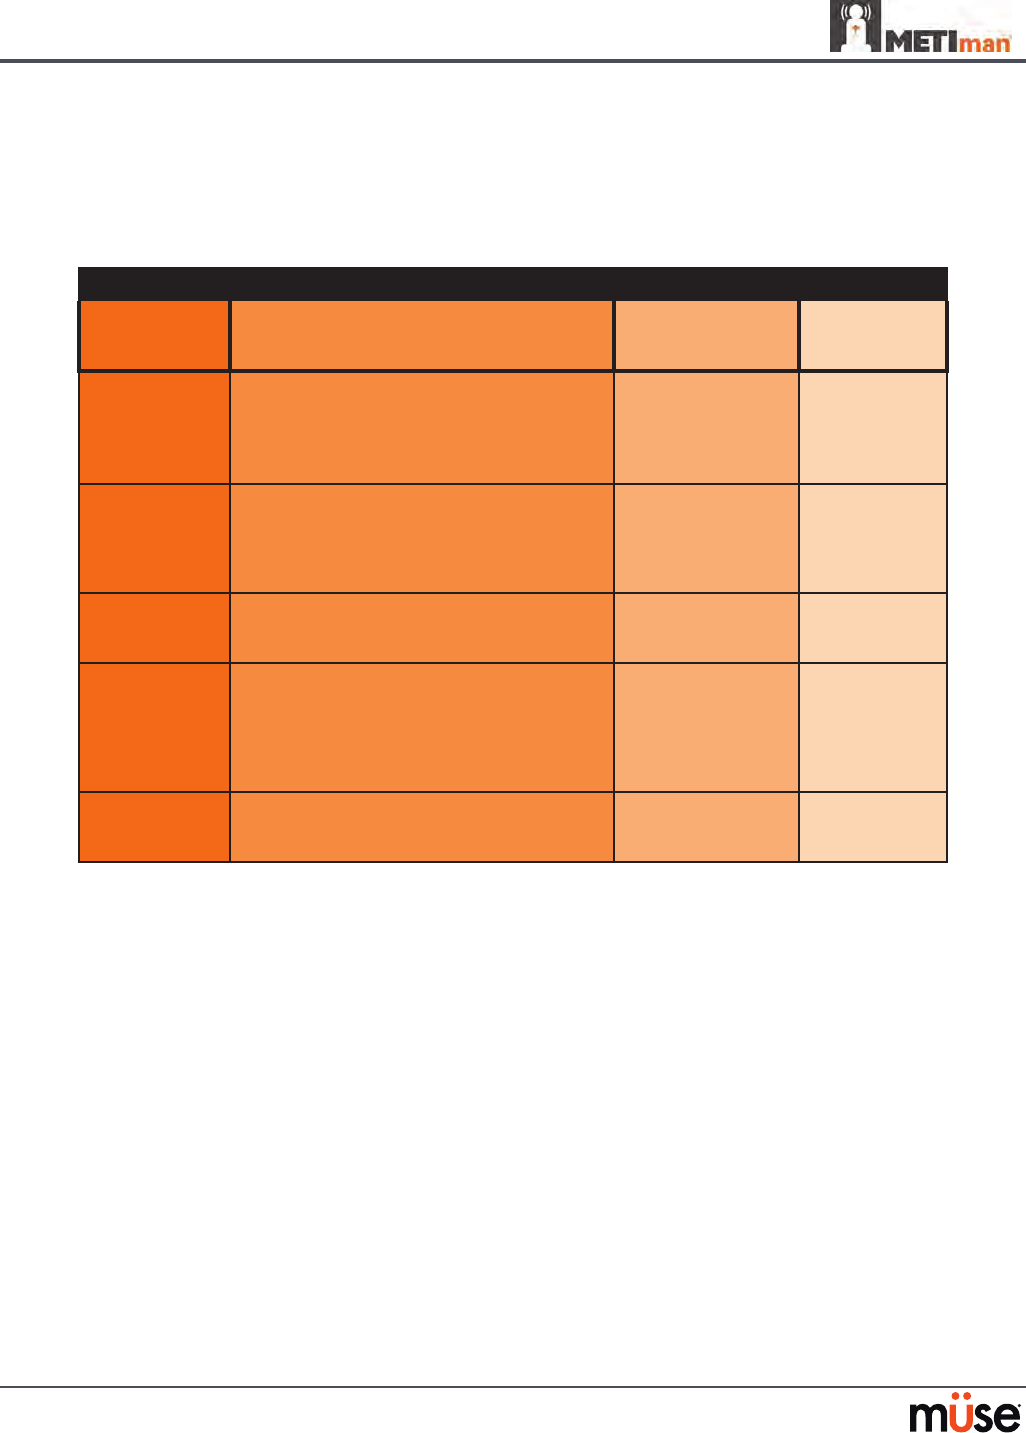

Airway Features

Anatomy, Physiology

and Clinical Signs Clinical Interventions, Patient

Monitoring and Scenarios. Software Control Manual

Control

Realistic Upper

Airway (Oropharynx,

Nasopharynx and Larynx)

(Prehospital only)

Allows direct laryngoscopy, oral and

nasal intubation and use of specialty

airway devices. Simulator detects

and responds appropriately to right

mainstem intubation. Endobronchial

intubation results in unilateral chest

excursion and breath sounds.

None required. None required.

Trachea, Left and Right

Mainstem Bronchi

(Prehospital only)

Tracheal intubation results in bilateral

chest excursion and breath sounds. None required. None required.

Airway Management and

Ventilation

Alveolar and arterial gas concentrations

appropriately reect the ecacy of

ventilation and oxygen administration.

Oxygen

administration input

by the instructor.

VIEW: Respiratory

None required.

Gastric Distention

(Prehospital only)

Esophageal intubation results in gastric

distension and the absence of breath

sounds, chest excursion and CO2 output.

None required. None required.

Breakaway Teeth

(Prehospital only)

Upper front teeth can be dislodged if

laryngoscopy is performed incorrectly. None required. See Breakaway

Teeth

Tongue Edema

(On/O)

Hinders, but does not prevent,

intubation. VIEW: Respiratory None required.

Posterior Pharynx

Swelling

(Prehospital only)

Obstructs view of larynx to prevent

intubation, but allows mask ventilation

“can’t intubate, can ventilate” scenario.

VIEW: Respiratory None required.

Laryngospasm

(Prehospital only)

Closes vocal cords and prevents

intubation and ventilation. When used

with posterior pharynx swelling, creates

a “can’t intubate, can’t ventilate” scenario.

VIEW: Respiratory None required.

Cricothyroid Membrane Allows needle cricothyrotomy,

transtracheal jet ventilation, retrograde

wire techniques and cricothyrotomy.

None required. See

Cricothyrotomy,

132